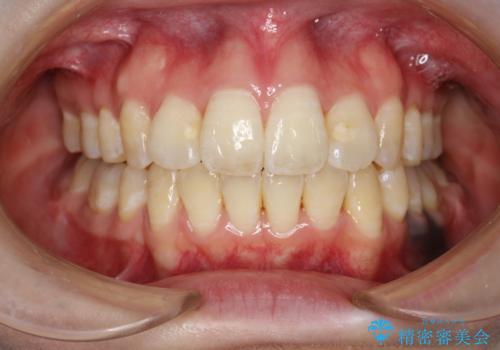

重度のガタガタ ワイヤーによる抜歯矯正

抜歯したスペースを使うことで、ガタガタと出っ歯を改善することができました。